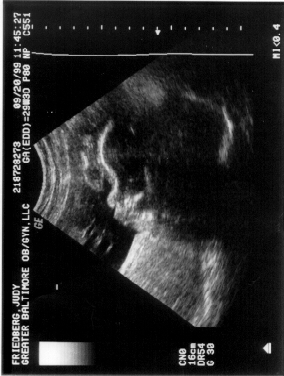

Here's what I used to look like!  Look at my photo album for newer stuff.